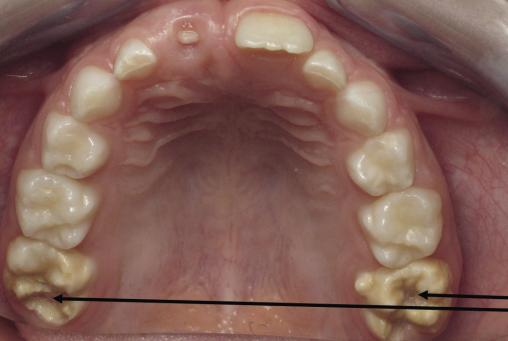

Atteintes MIH sur les premières molaires permanentes maxillaires (dents n° 16 et 26). Noter l’asymétrie des lésions et les pertes de substances.